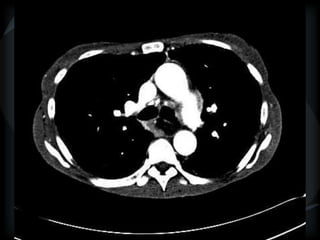

METS

random